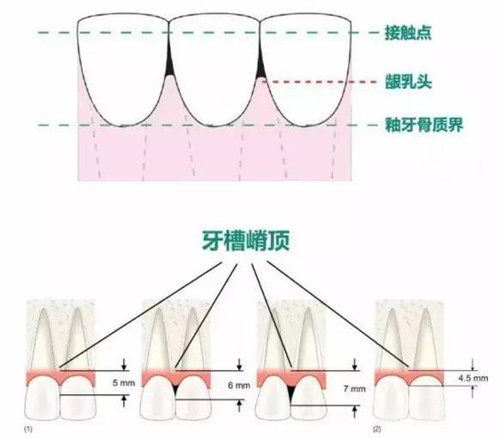

附加项目收费:牙槽骨骨粉填充 3200 元 / 次起(国产骨粉),上颌窦内提升手术 6500 元起(含可吸收膜),智能化种植导板设计费 1200 元 / 例(复杂病例需额外收取)